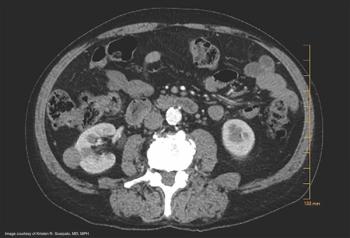

The authors discuss the case of a 57-year-old man who initially presents to a general surgeon with a chief complaint of right lower back and posterior neck pain, with associated soft tissue swelling. On presentation to the authors' institution, he had experienced regrowth of the masses with "ticking" in the right lumbar area that he correlated with his heartbeat. He also reported unintentional weight loss of 15 pounds over the previous 3 months.